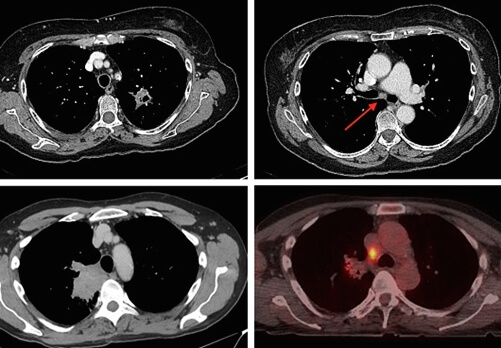

2.4. M(Metastasis)

마지막으로 M은 'Metastasis'의 앞글자로, '원격전이'를 뜻하는 말입니다. 원격전이가 있을 경우 암은 무조건 4기입니다. 만약 T1이나 T2처럼 원발성 폐암의 크기가 작더라도, 다른 장기로 원격 전이가 있을 경우에는 폐암 4기가됩니다.

2.4.2. M1

M1은 폐암이 다른 장기로 원격 전이를 했다는 뜻입니다. 즉, M1이 적혀 있으면 폐암 4기라고 생각을 하시면 됩니다. TNM 폐암 병기 구분 앞에 무엇이 적혀 있던, M1 이면 무조건 폐암 4기입니다.

폐암 4기는 생존율이 5% 미만입니다. 수술이 불가능하고, 항암치료로 생명 연장을 해야 합니다. 정말 정말 낮은 확률로 폐암 4기에 수술을 하는 경우도 있기는 합니다. 하지만 현대 의학기술로도 폐암 4기 완치는 아직까지 상당히 어려운 상태입니다.